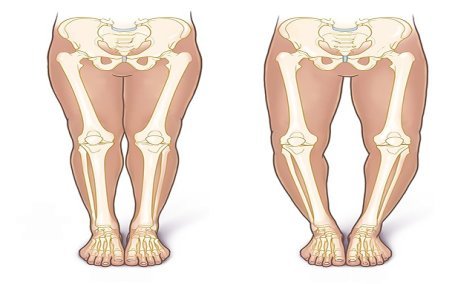

- Genu Valgum/Varum – Growth-guided leg corrections

GENU VALGUM

GENU VARUM